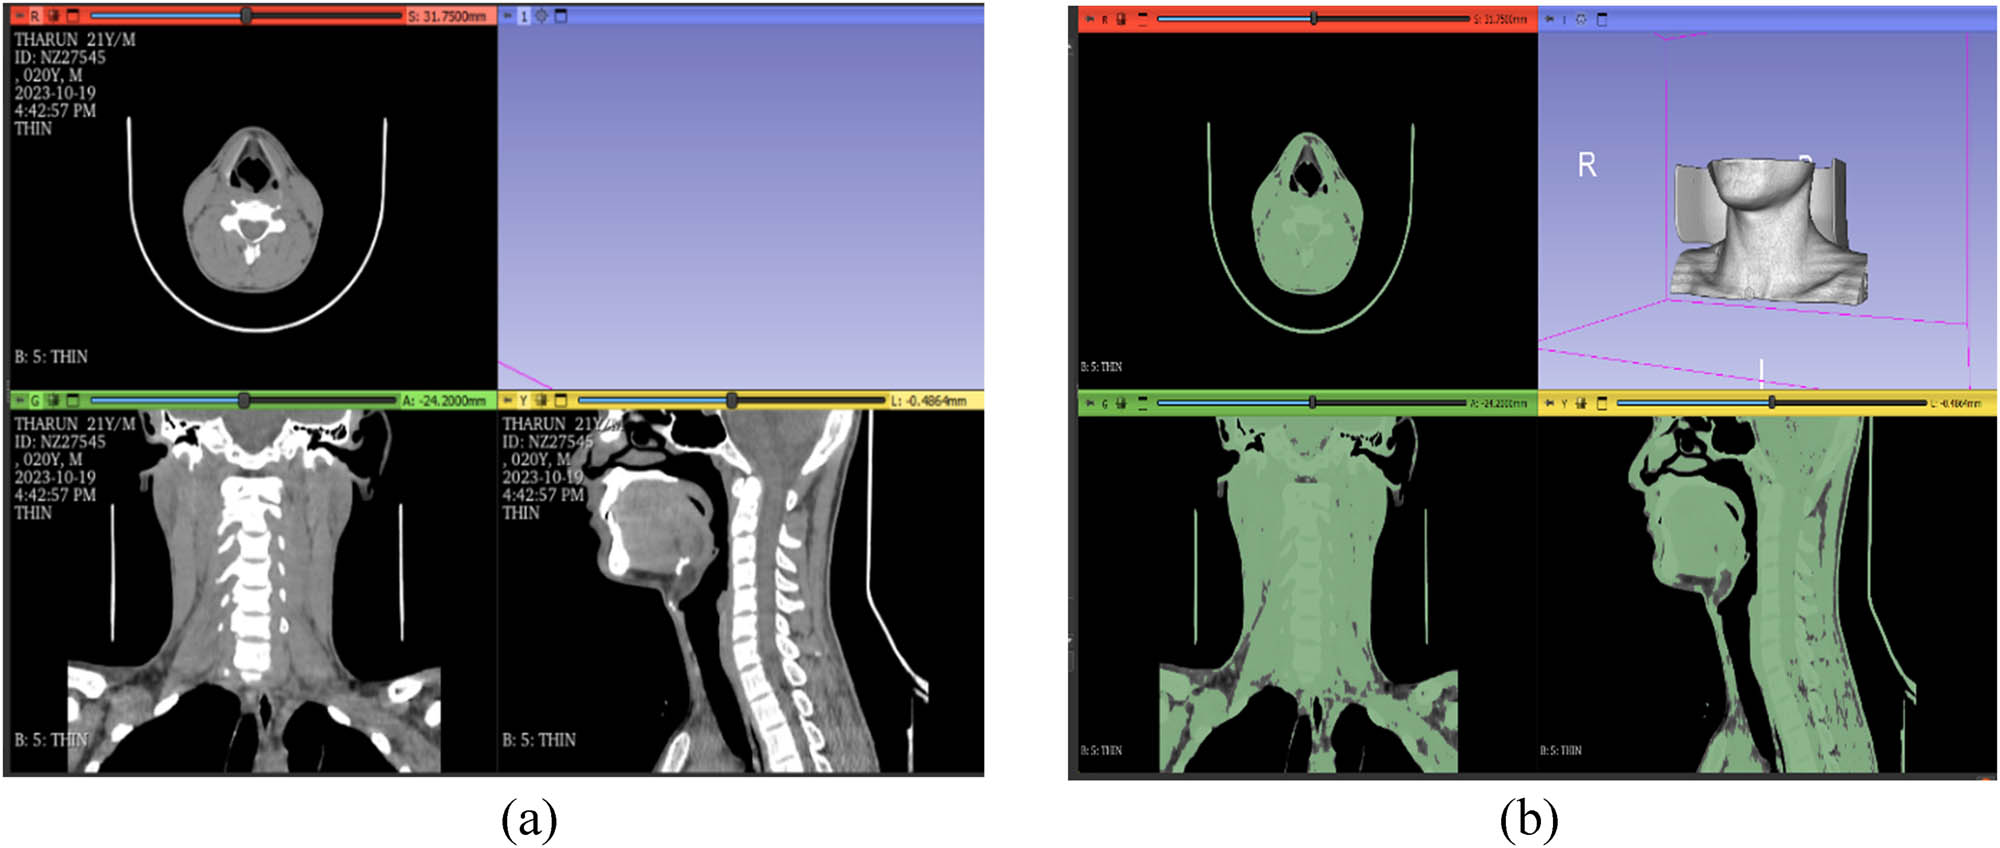

Using laser or 3D photogrammetric scanners, a digital depiction of an external human body component can be obtained. The neck region of a human body is scanned using 3D scanning technology to collect point clouds of data that serve as an input for modeling. Here, the acquisitions of a CT scan may also be used to create a 3D reconstruction [6,35]. This study involved a 22-year-old male patient with chronic neck pain persisting for over five years. CT scans of the cervical region were obtained using a Siemens SOMATOM Emotion 16-slice CT scanner at a certified imaging center to ensure precise anatomical accuracy, as shown in Figure 3(a). CT scanners save scanned data as images in the Digital Imaging and Communications in Medicine (DICOM) format. 3D Slicer is an open-source software that shows image volumes as three-dimensional objects using a volume rendering visualization tool [36]. The collection of neck photos was divided by threshold values that vary. Specifically, the first segmentation definition made use of the “thresholding” filter. The lower and upper criteria were used to define the object. The threshold function is chosen to turn the masked region into a 3D model by setting it to a changeable intensity range for the mask, as shown in Figure 3(b). The threshold values in this case were set between 5.21 and 2796.62. As shown in Figure 4(a), the model was modified to eliminate extra geometries and noisy components like bones, internal organs, or clothing using Segment Editor tools. This module of the 3D Slicer software finds segments, or structures of interest, in 2D, 3D, and 4D images. It is possible to display in two or three dimensions, create segmentation by interpolating or extrapolating segmentation on a small number of slices, make fine-grained visualization decisions, and edit on slices in any orientation [37]. The anatomical features of the cervical spine were studied. The procedure for transforming the segmented DICOM data into a standard triangulation language (STL) file is shown in Figure 5. Open loops and minuscule holes in the STL file were detected using the software Autodesk Meshmixer, as shown in Figure 4(b).

Cervical spine (a) DICOM format of CT scan images, and (b) cervical region in thresholding range.

Figure 3(a) and (b) shows the DICOM data file in 3D Slicer software along with the threshold values that were assigned. To improve the visualization of the neck region, the thresholds have been set at 5.21 and 2796.62 for the lowest and top values, respectively. Figures 4a and 5 show the presence of additional geometries and their removal, respectively. Sharp edges and apparent geometries were removed using scissors, and invisible geometries were removed with smoothing. Using Autodesk Meshmixer software, the open loops in the neck area were addressed during the DICOM to STL file conversion [41]. The recognition and correction of these open loops (small holes) are shown in Figures 4(b) and 5, respectively.